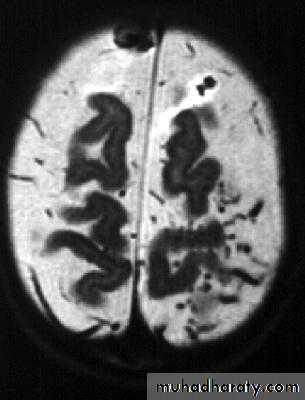

Bacterial Meningitis with cerebral oedema